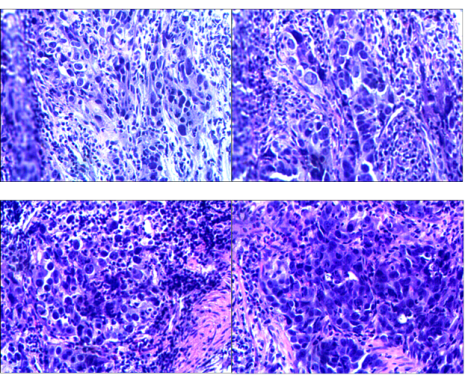

2021.02.24:外院胃镜活检组织病理切片提示胃角低分化腺癌,lauren分型:弥漫型。

图2 胃镜活检组织病理切片

胃镜检查(2021.6.9):慢性萎缩性胃炎C1伴糜烂(见图6)。

图6 胃镜